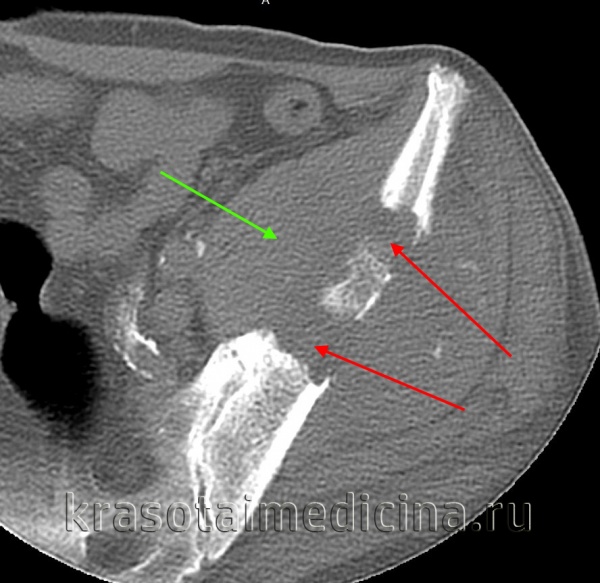

(Справа) КТ, аксиальная проекция, без контрастного усиления: ОО у этого же пациента располагается в переднем кортикальном слоев наряду с реактивным изменением калькара. (Слева) Рентгенография в ПЗ проекции: типичная ОО шейки бедренной кости у молодого человека. Литический очаг расположен в шейке бедренной кости и обусловливает выраженные реактивные изменения в виде уплотнения калькара и формирования остеофитов. Гнездо опухоли окружено небольшой зоной склероза, который при внутрикапсулярном расположении может быть менее выражен, чем при кортикально-диафизарной ОО.

(Справа) КТ, аксиальная проекция, без контрастного усиления: игла, установленная для проведения чрескожной термальной абляции ОО, расположенной в переднем кортикальном слое. (Слева) Рентгенография в ПЗ проекции: у пациента с анамнезом, позволяющим предположить наличие 00 визуализируется округлый очаг склероза, расположенный в медиальном кортикальном слое бедренной кости или сопряженно с ним. Обратите внимание на минимально выраженный склероз и отсутствие периостальной реакции, что позволяет отличить этот патологический очаг от обычной кортикальной ОО.

(Слева) Рентгенография в боковой проекции: кортикально-диафизарная ОО с выраженным утолщением заднего кортикального слоя большеберцовой кости. Утолщенная кость скрывает собственно гнездо опухоли

(Справа) КТ, аксиальная проекция, без контрастного усиления: у этого же пациента визуализируется задняя периостальная реакция в виде нагромождения, окружающая округлый литический очаг, глубоко погруженный в кортикальный слой. Эта ОО располагается непосредственно около питающего сосуда. Такое взаимоотношение наблюдается часто. (Слева) Рентгенография в боковой проекции: овальный литический очаг и окружающая его зона склероза В, которые позволяют диагностировать ОО.

(Справа) МРТ, корональная проекция, режим STIR: гнездо опухоли у того же пациента характеризуется типичным сигналом высокой интенсивности в режиме STIR. Обратите внимание на зону высокоинтенсивного сигнала в примыкающей надкостнице, а также в сопряженном участке костномозгового канала. Доброкачественное новообразование выглядит на МРТ, за счет таких реактивных изменений более агрессивно, однако соответствует ОО. (Слева) КТ, аксиальная проекция, без контрастного усиления: необычный пример ОО. На этом уровне визуализируется склерозированная корткальная кость, окружающая зону перелома. Возникает желание расценить патологическую область, как стрессовый перелом.

(Справа) КТ, аксиальная проекция, без контрастного усиления, срез выполнен немногодистальнее предыдущего: линия перелома ведет к необычного вида паталогическому очагу, расположенному под кортикальным слоем в костномозговом пространстве. Эта ОО привела к возникновению патологического перелома. Реакция кортикального слоя обусловлена обоими процессами.